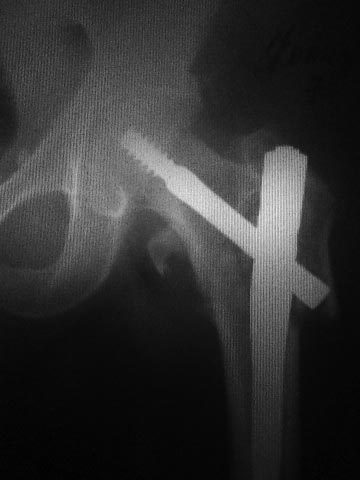

Доброго вечера, первичный снимок.

|

Может я не все понял, создаётся впечатление, что левое бедро синтезировали правым гвоздём.